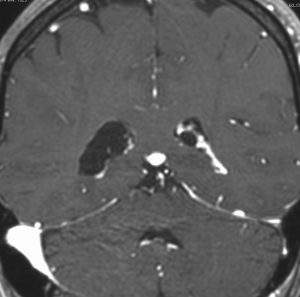

これも側脳室三角部の両側性の脈絡叢のう胞です。ガドリニウム増強で,脈絡叢が固まっていなくてばらけたように見えます。